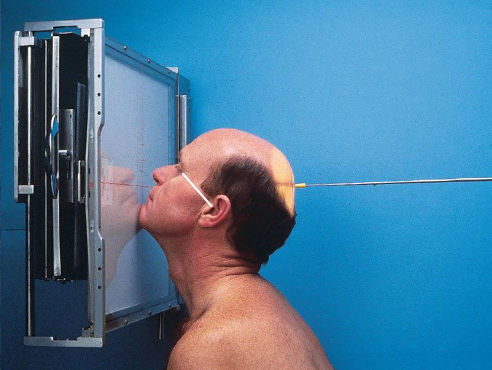

Parietoacanthial (Waters) facial bones

patient position:

prone or upright

center MSP to midline

part position:

rest head on tip of extended chin

nose slightly off IR

OML adjust to form 37 degree angle with IR plane

MML perpendicular to IR

MSP perpendicular to IR

IR centered to level of acanthion

respiration suspended

CR:

perpendicular, exits acanthion

collimation:

1 inch beyond the shadows of the lateral sides of the face, superiory to include the supraorbital margins, and inferiorly to the level of the chin

no larger than 8 × 10 inches